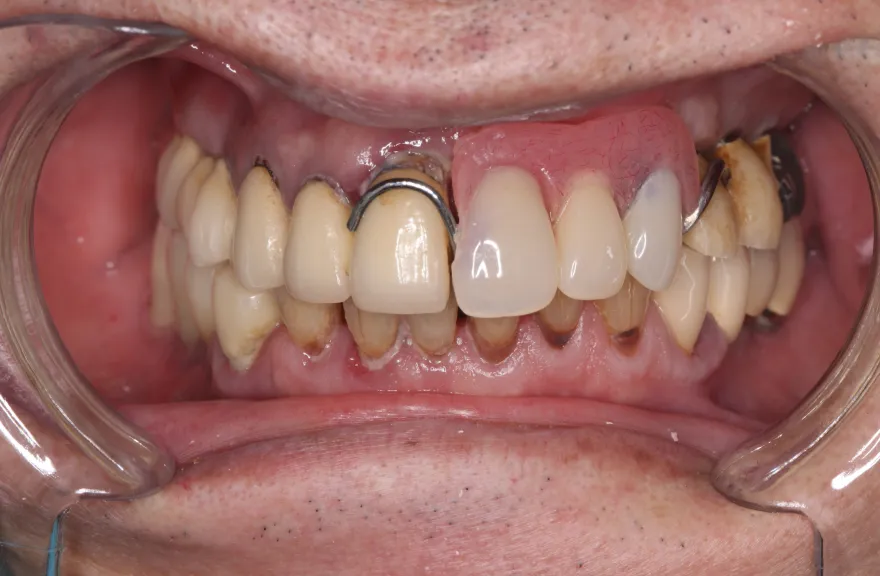

【治療例 3】奥歯が痛い、全体的にみて欲しい 60歳

- 相談内容

-

今まで何回歯を入れてもトラブルが起きるために、奥の歯を入れないまま今日に至る、ということでした。

噛み合わせ・骨格を読み解き、今後の人生でトラブルが起きにくいように全体的な治療計画を練りました。 - 治療費用・方針

骨格の前後的な差がある方でした。術前のレントゲンより、上下で歯牙の損傷に明らかな差があるのがみてとれます。

上の歯がないところにインプラント治療を行い、上顎は全てインプラントフィクスチャーによる固定性の歯を入れられることも費用的には可能な方でした。

しかし、治療において重要なのは今目の前の歯を見ることではなく、なぜ目の前の歯になったかを考え、未来へ活かすことです。

骨格的な前後差を考慮することなく歯をいれても、装着した人工物は決して長持ちしません。

今回の症例では、敢えて上顎は総義歯形態をとり、骨格的な前後の差を解消するよう工夫しました。

上顎の残っていた歯も、差し歯としては使えずとも、敢えて根だけ残すことによって組織を温存し、義歯の安定に寄与するよう設計しました。

ここまで全体的にしっかり治療しておけば、今後の人生においてトラブルになるようなことにはならないでしょう。 - 治療のリスク